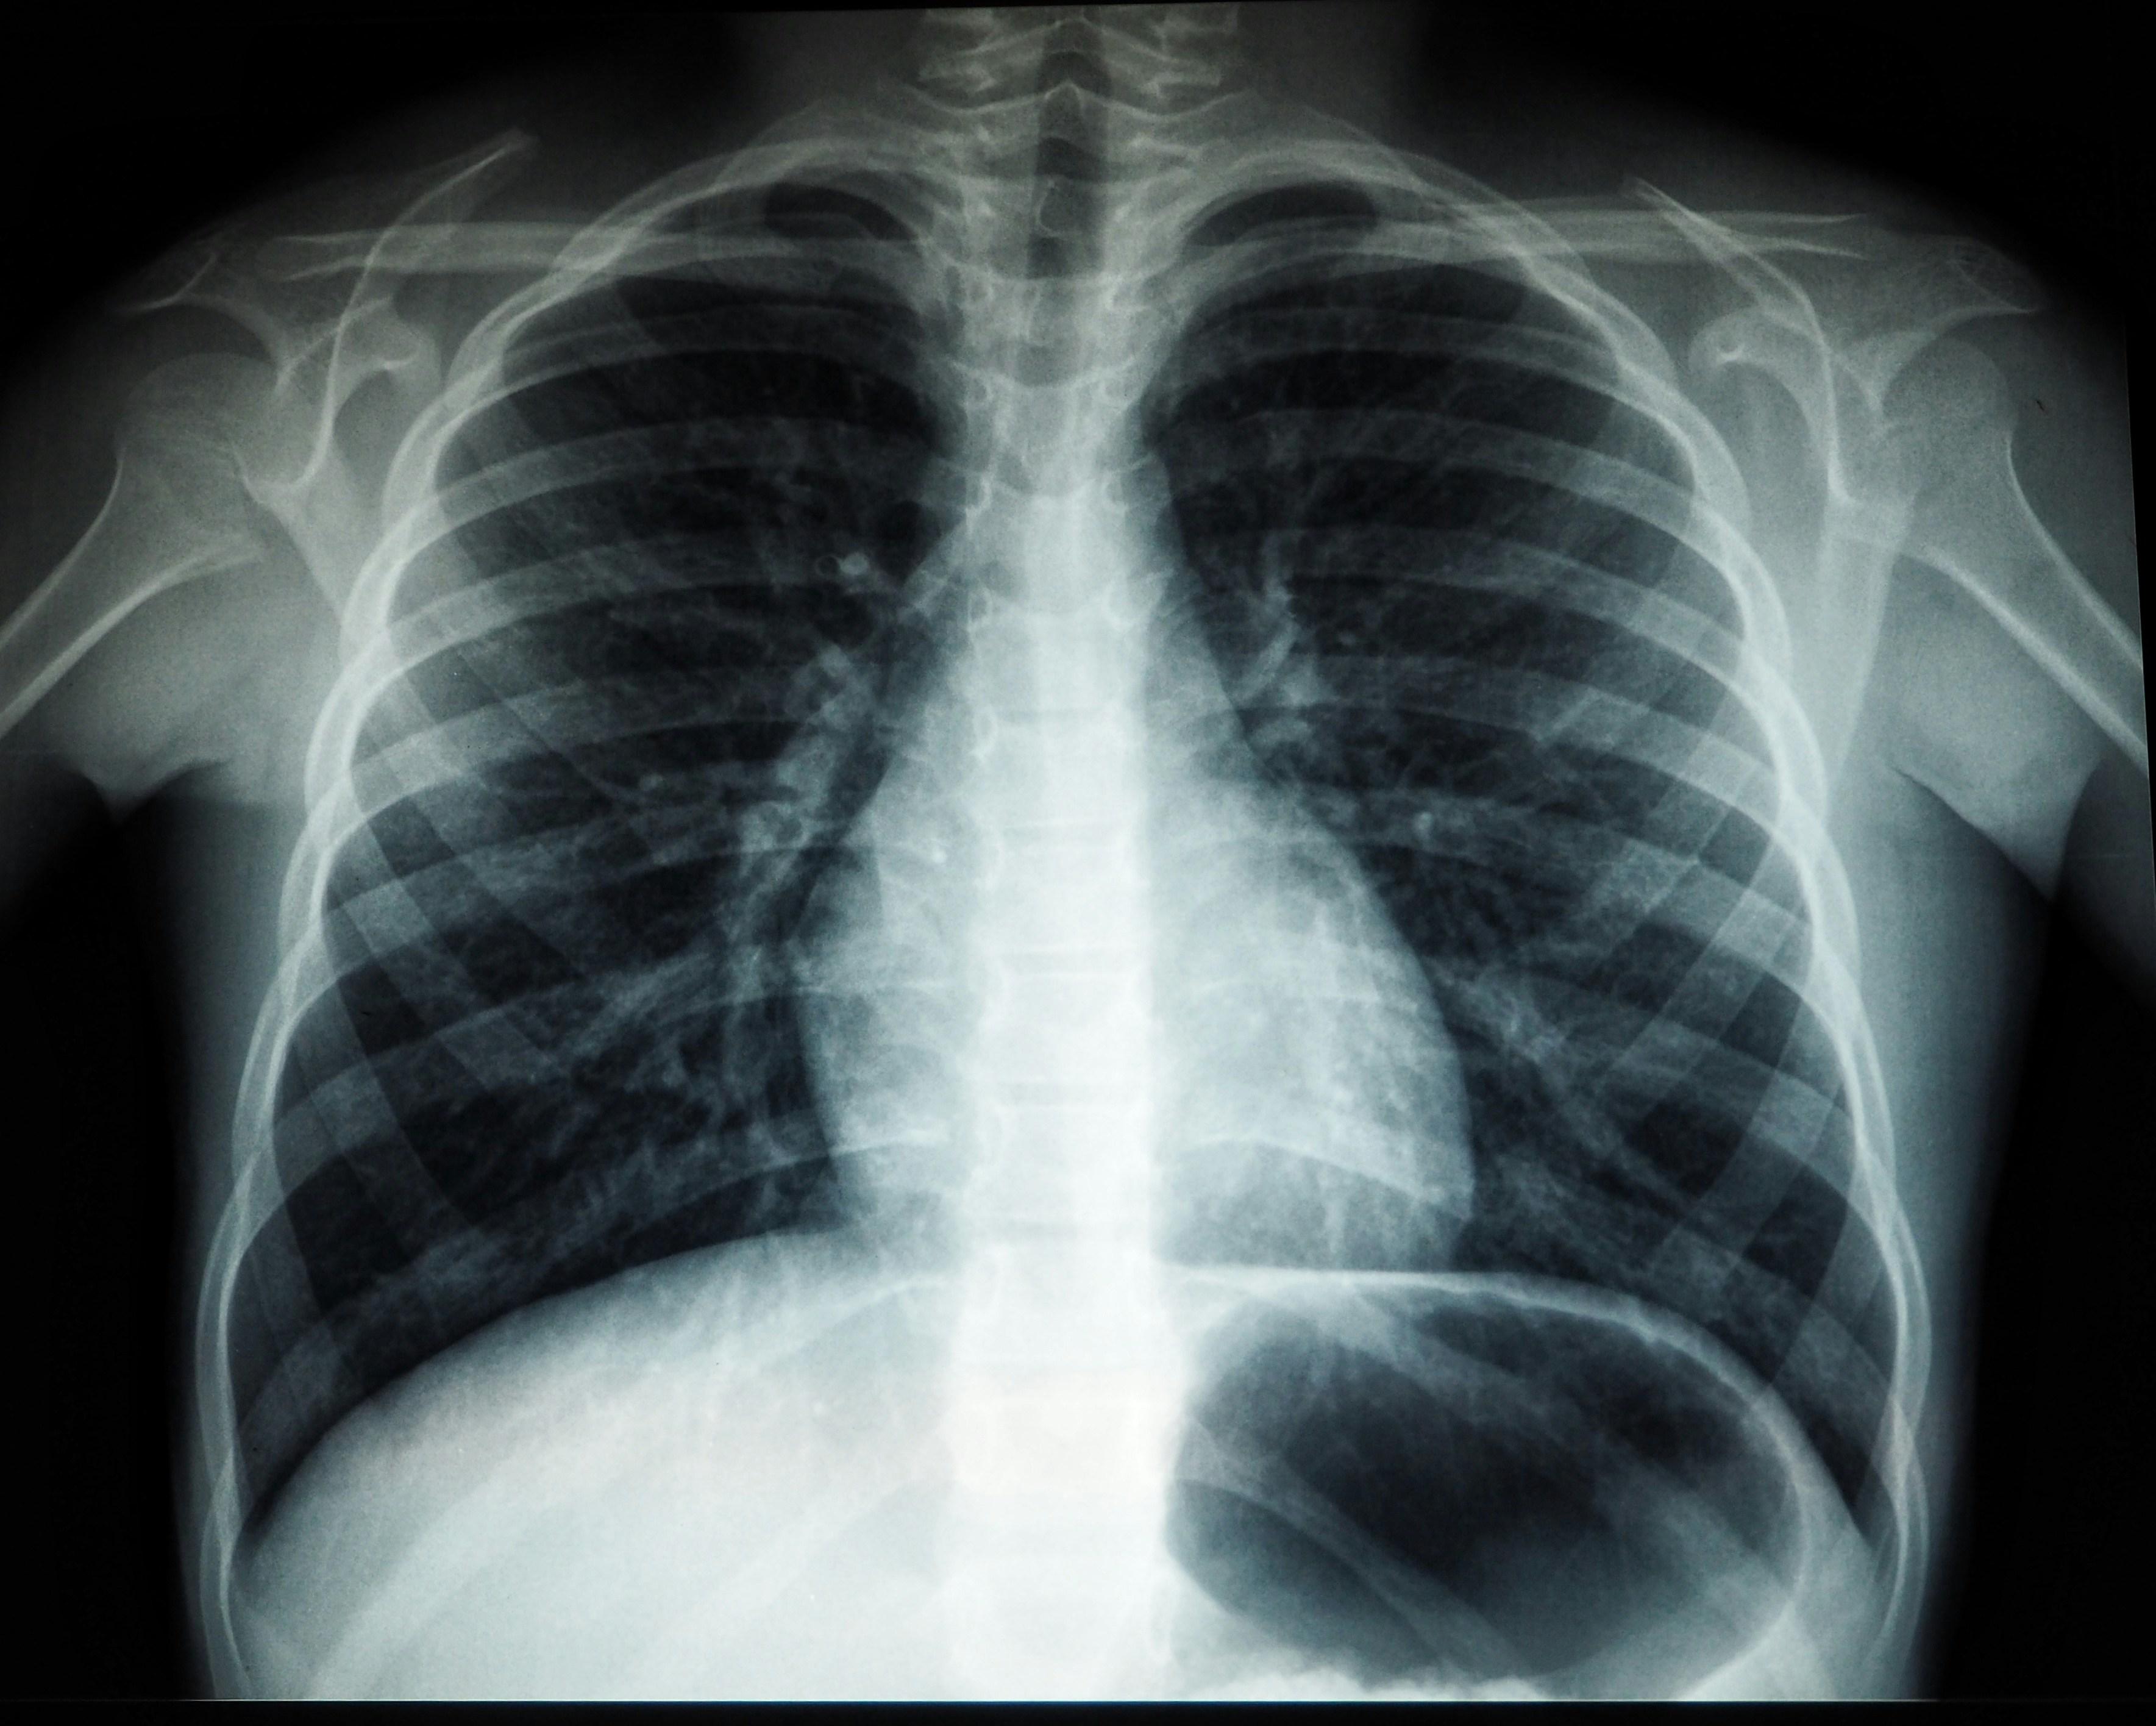

निमोनिया असल में फेफड़ों में सूजन की बीमारी है, जो बैक्टीरिया, वायरस या फंगल संक्रमण से होती है. यह रोग खासतौर पर छोटे बच्चों, बीमार लोगों और बुजुर्गों के लिए खतरनाक होता है, क्योंकि उनका शरीर संक्रमण से लड़ने में कमजोर होता है.

निमोनिया फेफड़ों में होने वाला एक गंभीर संक्रमण है, जो लंग्स की हवा भरी थैलियों में सूजन पैदा कर देता है. इस सूजन के चलते इन थैलियों में पस या तरल पदार्थ भरने लगता है, जिससे खांसी, तेज बुखार, ठंड लगना और सांस लेने में परेशानी जैसी दिक्कतें होती हैं. अगर समय पर इलाज न किया जाए, तो यह संक्रमण फेफड़ों से आगे बढ़कर शरीर के अन्य हिस्सों को भी प्रभावित कर सकता है और जानलेवा रूप ले सकता है.